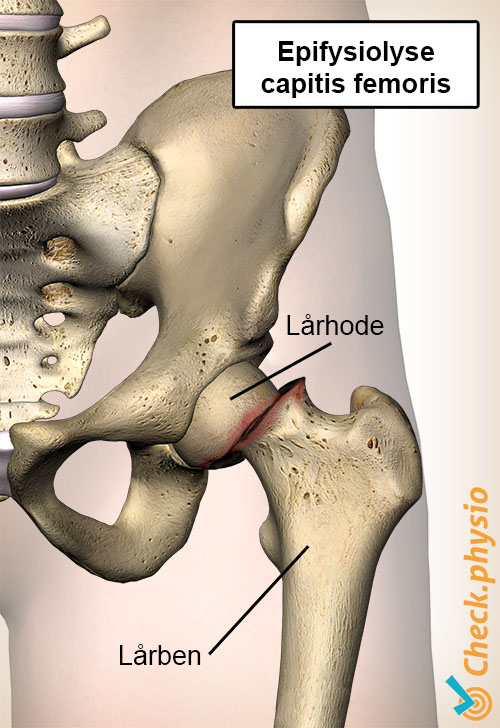

Epifysiolyse capitis femoris er et hofteproblem som oppstår når hoftekulen glir av lårbeinet. Tilstanden ses oftest hos barn mellom 10 og 15 år. Den kan ramme det ene beinet, men kan også forekomme på begge sider. Tilstanden er sjelden og blir derfor ofte oversett.

Epifysiolysis capitis femoris oppstår vanligvis i en periode med rask vekst, kort tid etter pubertetsstart. Av uklare årsaker svekkes vekstplaten som ligger under hoftekulen. Som følge av dette forskyves lårbeinet oppover og fremover i forhold til hoftekulen. Dette kan skje akutt eller gradvis. Når et barn er ferdig utvokst, er vekstplaten forbenet, og hoftekulen kan da ikke lenger gli ut.

Diagnosen stilles basert på pasientens historie og en fysikalsk undersøkelse, der det viser seg at bevegeligheten i hoften er nedsatt og smertefull. For å bekrefte diagnosen tas det røntgenbilder, hvor en avglidning av lårbeinshodet (ved epifysiolysis capitis femoris) kan observeres.